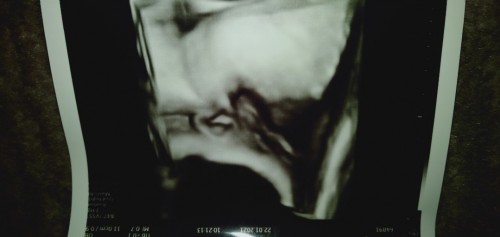

Bun ini biang keringat kah? Bintik putih kaya ada airnya Kasian bayi saya baru seminggu udah ada kaya gitu dibagian kepala sama jidatnya aja. Sudah saya kasih sabun lactacid baru 2 hari Biang keringat kadang smpe brp lama Bun? Atau ada saran lain kah dipakein apa?#seriusnanya #bantusharing